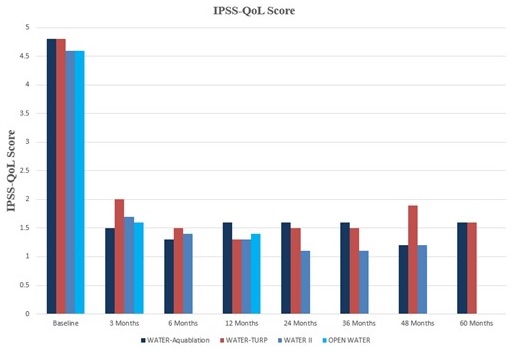

alternative resective procedures. In our U.S. pivotal trial, Waterjet Ablation Therapy for Endoscopic Resection of prostate tissue, or the WATER study, Aquablation therapy demonstrated superior safety and non-inferior efficacy results compared to transurethral resection of the prostate, or TURP, the historical standard of care for the surgical treatment of BPH. In the WATER and WATER II studies, surgical retreatment rates were only 5.2% at five years and 3.0% at four years, respectively. In the OPEN WATER study, there were no surgical retreatments at one year. The retreatment rates in the WATER and WATER II studies compare favorably to surgical retreatment rates observed for alternative treatments for BPH. One study published in the BJU International Journal reported on 52,748 men undergoing TURP or PVP with an approximated three-year freedom from surgical retreatment of 92% and 89%, respectively. A second study published in the Journal of Urology reported on 43,041 men undergoing TURP, PVP, enucleation, or open simple prostatectomy with an approximated three-year freedom from surgical retreatment of 93%, 89%, 94%, and 96%, respectively.

•Favorable safety profile. Aquablation therapy has demonstrated low rates of irreversible complications, including urinary incontinence, erectile dysfunction and ejaculatory dysfunction, compared to published rates observed for other resective surgeries. In our WATER study, patients who underwent Aquablation therapy maintained a higher level of sexual function compared to those who underwent TURP.

Clinical diagnosis of BPH typically involves a number of tests that are used to assess the degree of LUTS and determine whether the symptoms are caused by BPH or another condition. A symptom score index utilizes standardized questionnaires to quantify a patient’s degree of LUTS. One of the most common scoring systems is the International Prostate Symptom Score, or IPSS. Using this scoring system, LUTS are classified as either mild, moderate or severe. The IPSS questionnaire is a key tool used to evaluate treatment options and assess treatment success. Other commonly used tests include a digital rectal exam, urine sample tests, imaging scans, blood tests and uroflowmetry tests, which measure the strength and amount of urine flow during urination. Patients suffering from symptoms of BPH are typically first seen by a primary care physician, who may diagnose and manage the patient, or refer the patient to a urologist. A urologist is a physician who specializes in diseases of the urinary tract in both males and females as well as the male reproductive system. Urologists are trained to perform surgery for various types of urologic conditions, including BPH.

BPH Treatment Options

The main goal of BPH treatment is to alleviate the symptoms associated with the disease and improve the patient’s quality of life. As such, a patient’s recommended course of treatment is largely based on the patient’s degree of symptoms, typically measured using validated scoring systems such as IPSS. Patients with mild symptoms who have not developed other complications of BPH may choose watchful waiting, meaning that before proceeding with active treatment, the physician and patient wait to see if symptoms get worse or if new symptoms develop. Patients who choose this approach are generally advised to implement lifestyle changes and return for yearly visits with their physician to determine if symptoms are changing. For most men, the prostate will continue to grow and symptoms will worsen. As symptoms become more bothersome, active treatment may be recommended. The two primary categories of active treatment for BPH are drug therapy and surgical intervention.